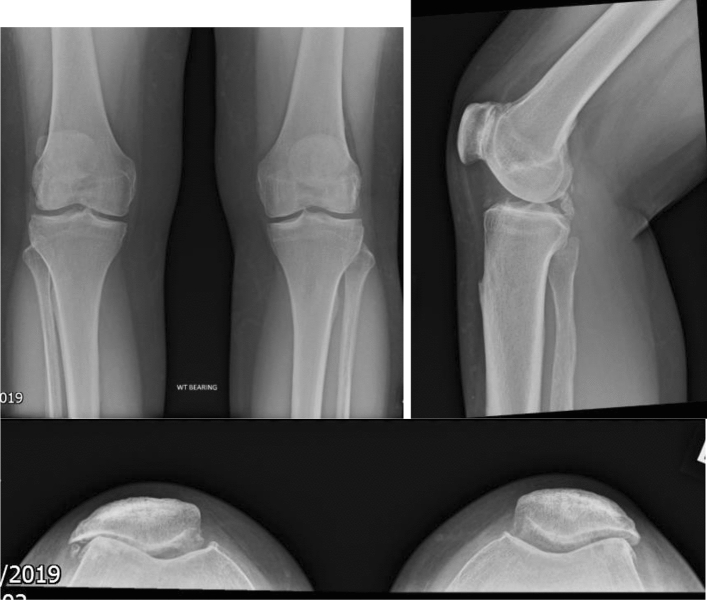

Patient selection for PFJ replacement is crucial. Patients must have a normal PFJ alignment with an isolated non-inflammatory PFJ arthritis which causes persistent pain and daily activity limitations. There should be evidence of significant OA on plain radiographs AP, lateral and skyline (Fig. 1). Most patients will have a MRI scan pre-operatively to ensure this is isolated disease (Fig. 2). The clinical picture should fit the radiological findings. They should have undergone a period of non-operative management such as analgesia and physiotherapy. Contra-indications or PFJ replacements are active infection elsewhere, inflammatory arthritis, significant OA (bone on bone) in the medial or lateral compartments. Some degree of lateral or medial compartment wear is acceptable if the PFJ replacement is in a young patient as part of a staged life long compartmental resurfacing strategy. Obesity has been shown to be a poor prognostic indicator [9]. There is no evidence age influences the outcomes of PFJ replacements, therefore there is no age limit to performing a PFJ replacement and in fact the lower morbidity and mortality associated with partial knee replacement makes this an attractive solution in the older patient as long as the inclusion criteria are met.

Fig. 1.

AP, lateral and skyline views of PFJ OA